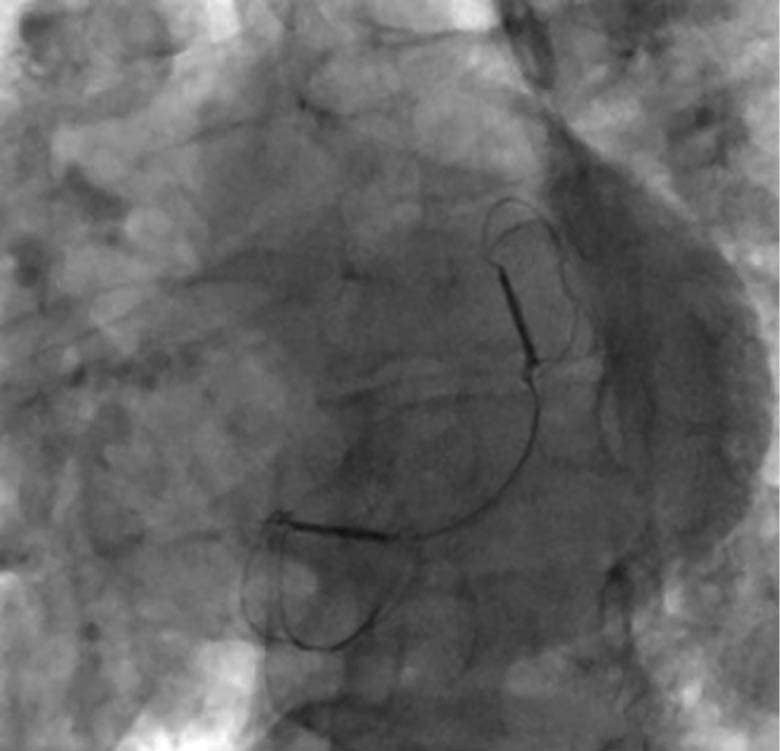

Intraprozedurales Sizing unter Fluoroskopie während eines interventionellen kardialen Eingriffs zur Anpassung eines Implantats.

Abbildung 3b: intraprozedurales „Sizing“

unter der Fluoroskopie

Fluoroskopische Darstellung des Endergebnisses nach Implantation des CARILLON®-Systems bei Mitralklappeninsuffizienz.

Abbildung 3c: Endergebnis des CARILLON®-Systems

Die Implantation eines 60-mm-Carillon®-Systems erfolgte unter fluoroskopischer und TEE-gestützter Kontrolle nach vorheriger intraprozeduraler Größenauswahl und Anpassung in Analgo-

sedierung. Die Implantation verlief komplikationslos. Eine angiographische Kontrolle schloss eine relevante Kompression des RCX und der RCA aus. Die Interventionsdauer betrug 45 Minuten, die Durchleuchtungszeit 11 Minuten.